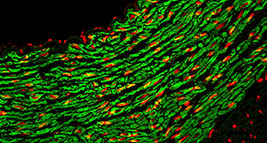

8�����、免疫熒光染色

免疫熒光技術(shù)就是將不影響抗原抗體活性的熒光色素標(biāo)記在抗體(或抗原)上����,與其相應(yīng)的抗原(或抗體)結(jié)合后���,

在熒光顯微鏡下呈現(xiàn)一種特異性熒光反應(yīng)����。